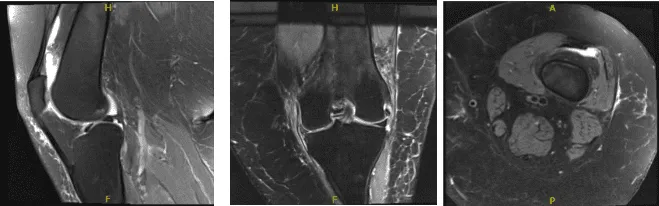

Las resonancias magnéticas fueron revisadas y comentadas por el médico; No hay fractura aguda ni osteonecrosis. Probablemente es reactivo un esguince moderado del ligamento colateral medial/desgarro parcial. Por lo demás, los ligamentos cruzados y colaterales están dentro de los límites normales.

El menisco lateral está intacto. Se identifica fisuración cartilágica de grosor total focal en la meseta tibial lateral posterior con edema subcondral leve. Hay un aumento de la anomalía intrasustancial en el cuerpo y en el cuerno posterior del menisco medial, con una rotura radial incompleta en la unión cuerpo-cuerno posterior.

No se ve ningún fragmento desplazado. La unión de la raíz posterior está intacta. Hay un adelgazamiento moderado del cartílago central que soporta el peso. Compartimento patelofemoral: Hay rótula alta e inclinación patuliana lateral. Se observa un ablandamiento del cartílago rotuliano sin defecto de grosor total.

Un edema leve en el músculo gastrocnemio lateral de la cabeza puede reflejar una leve tensión en la cabeza. No se observa atrofia muscular desproporcionada de alto grado. Los tendones imagados, incluido el mecanismo extensor, están intactos. Hay un pequeño derrame articular. No se agradece el quiste poplíteo.

No hay cuerpos sueltos intraarticulares y sueltos. El edema subcutáneo es inespecífico, las estructuras neurovasculares muestran una evolución normal. Desgarro del menisco medial y esguince/desgarro del ligamento colateral medial. En otros lugares, más pronunciados en el compartimento medial. Pequeño derrame articular.

Resonancia magnética de rodilla izquierda sin contraste